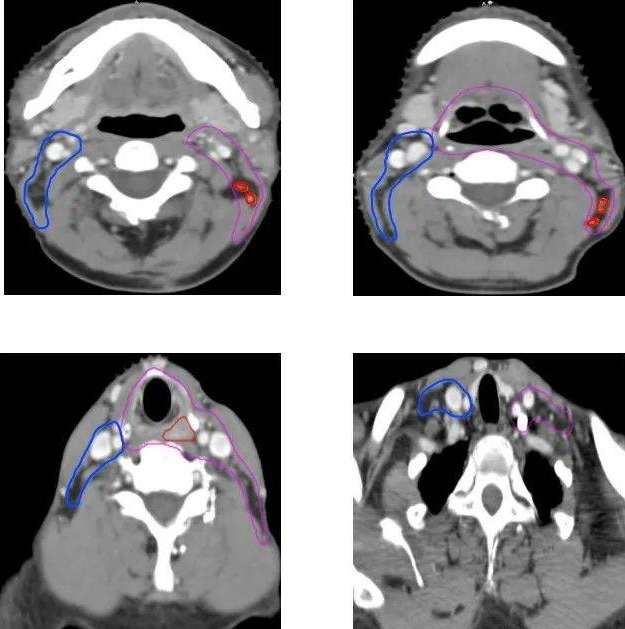

病例二:术后辅助放疗(下咽鳞癌T2N2bM0 IVA期,右侧梨状窝,右颈II-III区淋巴结转移

CTV1为高危亚临床病灶(包括术后瘤床区、同侧II-V淋巴引流区,全喉及相邻会厌前间隙,椎前筋膜间隙)

CTV2为低危亚临床病灶(包括双侧咽后淋巴结及对侧II-IV区淋巴引流区)